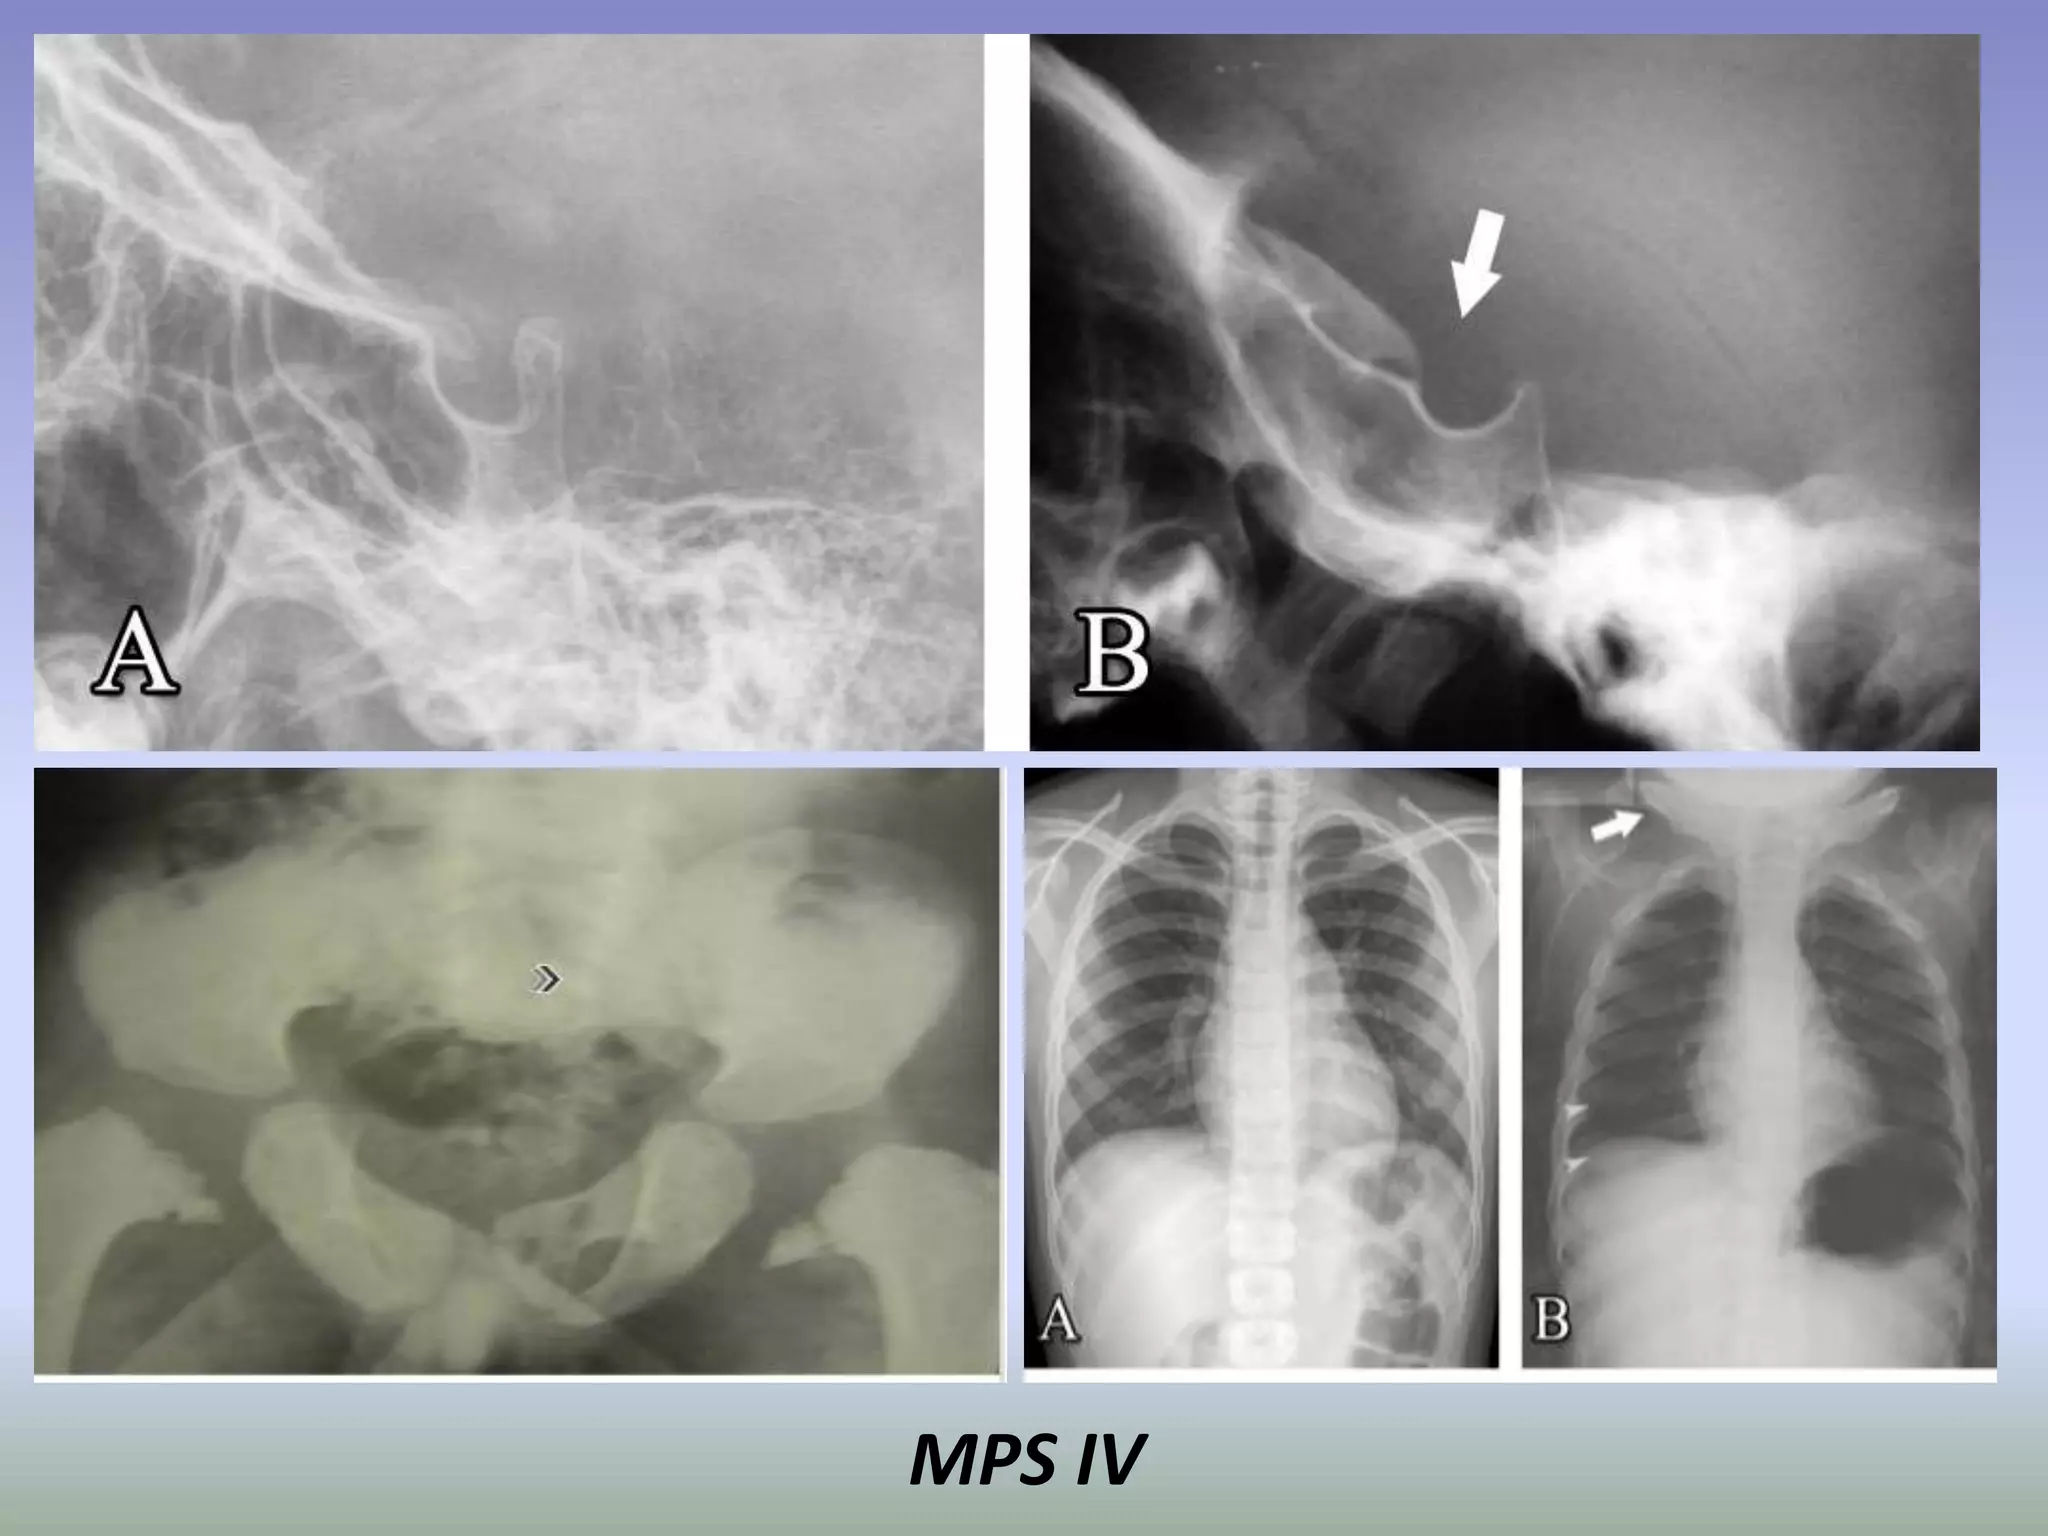

Mucopolysaccharidosis

type IV.

MPS IV